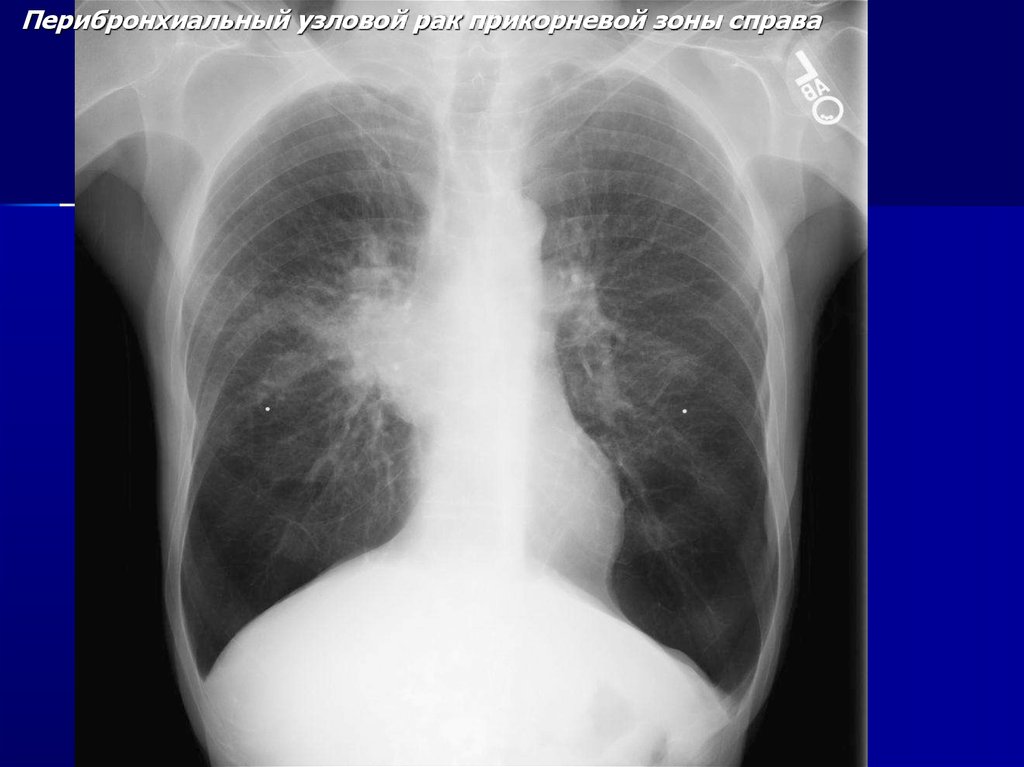

Перибронхиальный узловой рак прикорневой зоны справа